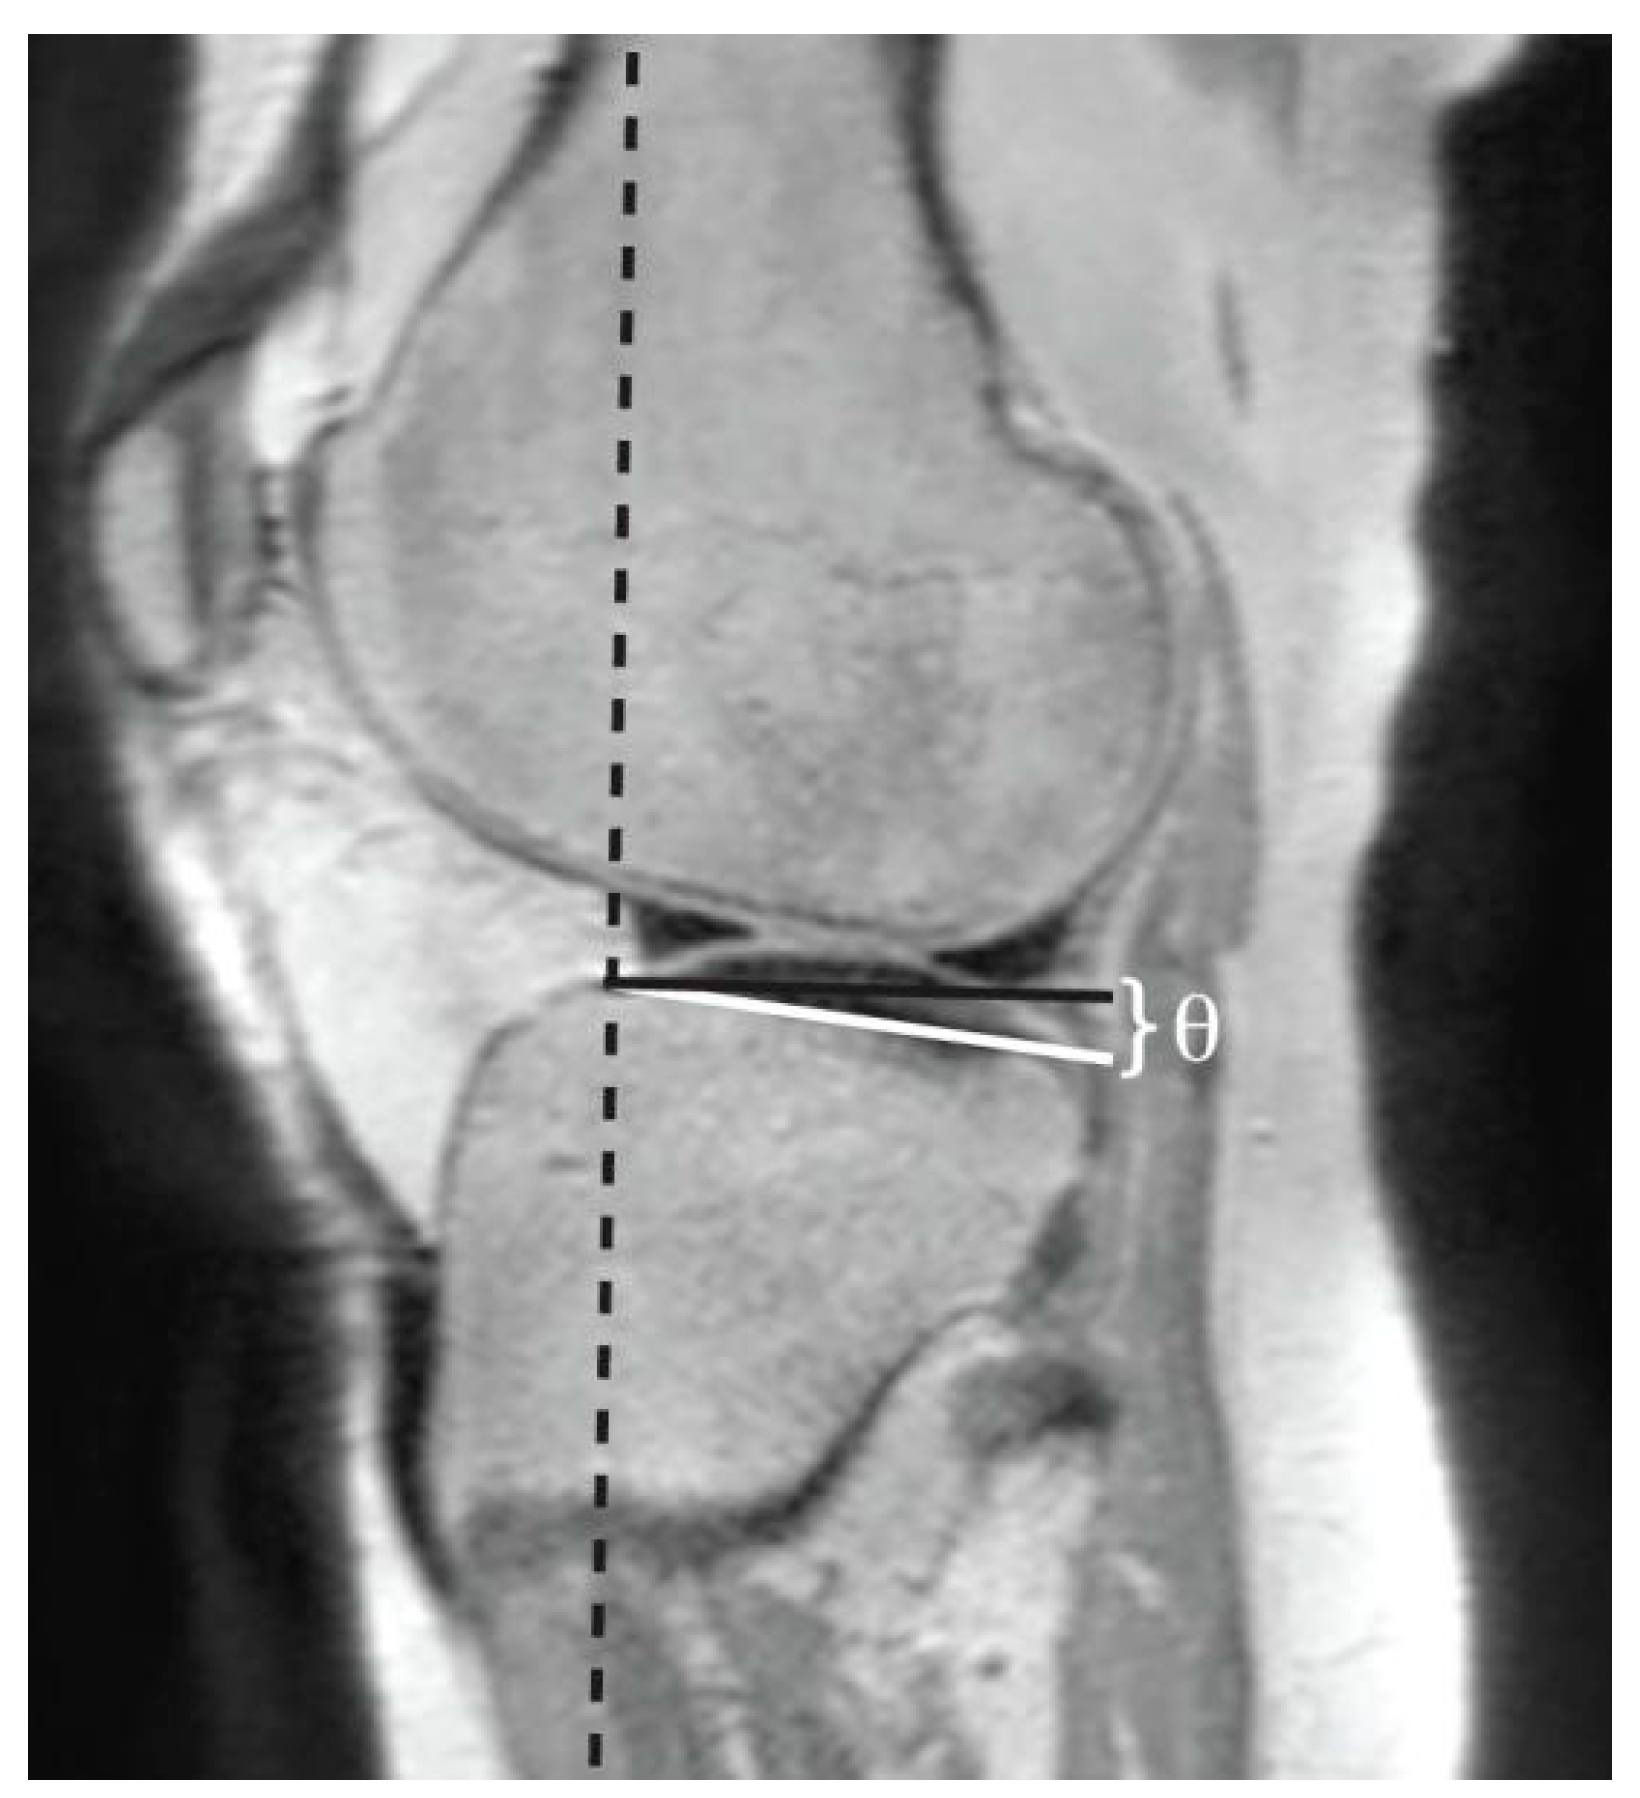

Measurement of Lateral Posterior Tibial Slope

- Lipps DB, Wilson AM, Ashton-Miller JA, Wojtys EM. Evaluation of different methods for measuring lateral tibial slope using magnetic resonance imaging. American Journal of Sports Medicine. 2012;40(12):2731-2736. [CrossRef]

- Hudek R, Schmutz S, Regenfelder F, Fuchs B, Koch PP. Novel Measurement Technique of the Tibial Slope on Conventional MRI. Clin Orthop Relat Res. 2009;467(8):2066. [CrossRef]